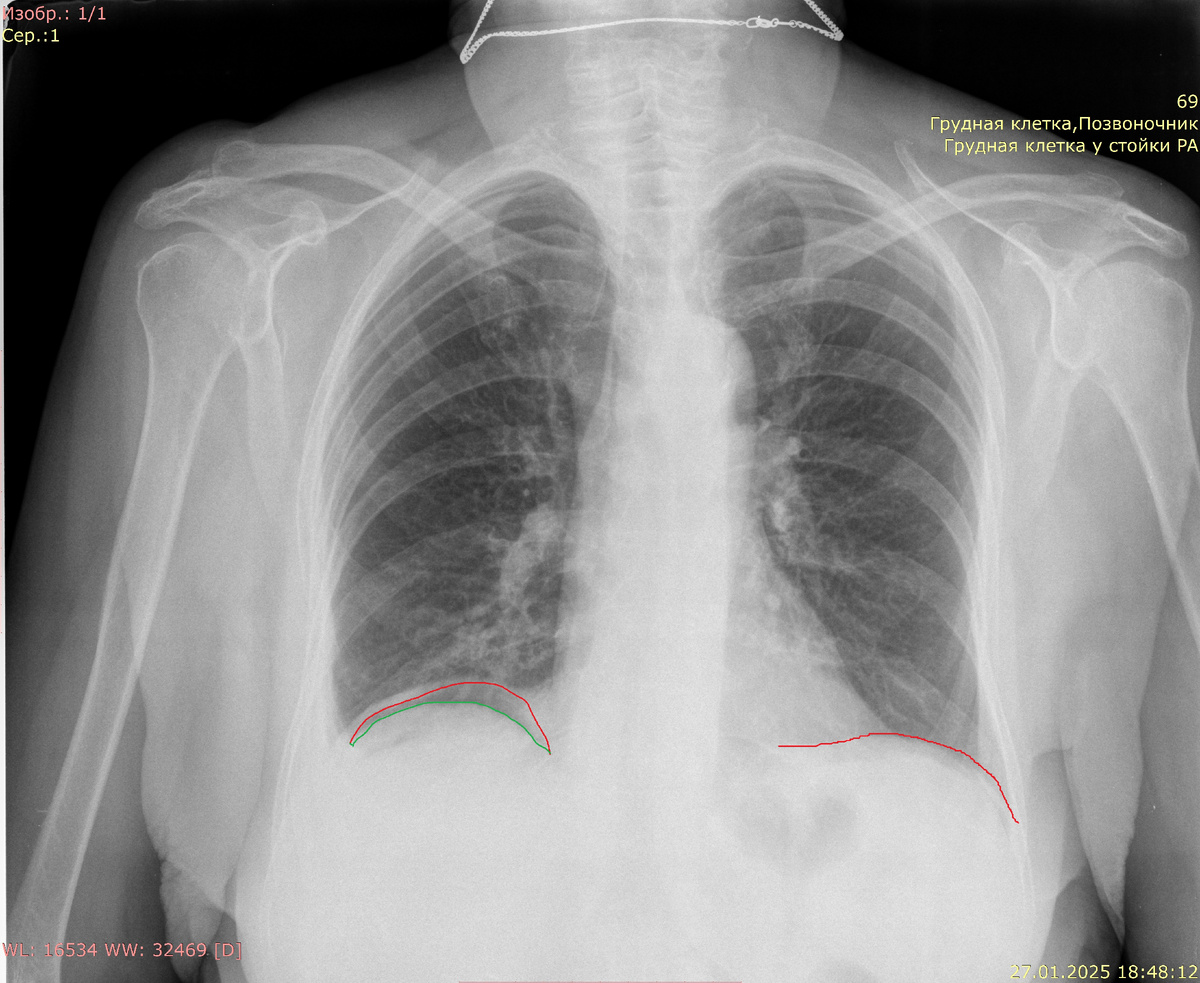

При перфорации полого органа, такого как кишечник или желудок, воздух может накапливаться под диафрагмой, что визуализируется на рентгенограммах в виде пузырьков газа. Эта находка обычно указывает на необходимость неотложной хирургической помощи, так как она может сигнализировать о высокой степени угрозы для жизни пациента. На рентгенологических изображениях свободный газ проявляется как области с пониженной плотностью, чаще всего расположенные под правым или левым куполом диафрагмы. Это связано с анатомическими особенностями расположения органов в брюшной полости, где газ имеет тенденцию подниматься к верхним участкам.

Диафрагма красная, верхний край печени зеленый. Между ними газ - симптом "серпа".